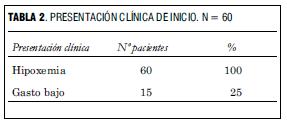

Todos los pacientes se presentaron con hipoxemia, 25% presentó, además, gasto bajo que requirió las correspondientes medidas de compensación (tabla 2).

Todos se presentaron con hipoxemia y 25% presentó, además, signos de bajo gasto. Dos tercios eran D-TGA simples y un tercio se presentaron como D-TGA complejas (todas con comunicación interventricular) asociando coartación de aorta e hipoplasia del arco aórtico en un caso, estenosis subpulmonar leve en un caso y situs inversus en un caso. En 76% la distribución coronaria fue tipo A1 de Leiden, en 15% tipo A2 y en 9% para los tipos restantes. Todos recibieron prostaglandina E1 y fueron sometidos a Rashkind. En cuatro casos fue necesaria la administración de óxido nítrico para lograr una saturación adecuada. A todos se les practicó la cirugía de switch arterial.

We report the outcome, complications and approach in 60 patients submitted to arterial switch surgery for D-transposition of the great arteries, after hospital discharge. We performed a mean follow-up of 5 years and 6 months (age range: 4 months to 11 years old) in a group of patients with these characteristics at admission time: 60% male, 25% with weight inferior to 3 kg (minimum: 1.830 g). All presented hypoxemia and 25% also showed symptoms of low cardiac output. 2/3 represented simple D-TGA cases and 1/3 complex D-TGA cases (all showed interventricular communication) with aortic coarctation and aortic arch hypoplasia in one case, mild pulmonary stenosis in one case and situs inversus in one case. 76% of the cases presented a Leiden type A1 coronary distribution, 15% presented type A2 and 9% of other types. All received E1 Prostaglandin and Rashkind. Nitric oxid administration was necessary in four cases in order to reach an appropriate saturation level. All were submitted to arterial switch surgery. After discharge, we performed both a clinical and a paraclinical follow-up through ECG, color doppler ultrasound, Holter and Ergometry studies. 80% showed a positive evolution. In this group, trivial residual damage prevailed (pulmonary or aortic supravalvular stenosis, aortic, pulmonary, mitral or tricuspid insufficiency). Nine patients (15%) required additional interventions: pulmonary artery plasty in seven cases (11,6%), in one case surgery for residual interatrial communication surgery was needed, in another case, resection of subaortic stenosis was performed. Three patients died (5%) with dilated cardiomyopathy; one of them having underwent a pacemaker implantation, the other having underwent mitral valve replacement.